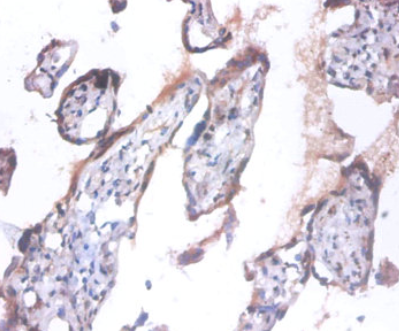

免疫組化實(shí)驗(yàn)案例:

圖:使用ANAPC5抗體(稀釋度為1:100)對(duì)石蠟包埋的人胎盤(pán)組織進(jìn)行免疫組化染色。